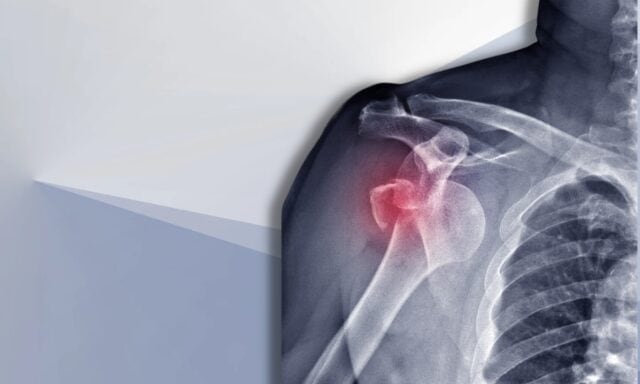

În acest episod vom vorbi despre toate lucrurile legate de instabilitatea umărului. Veți afla mai multe despre clasificarea Stanmore și daunele structurale după luxații. Vom discuta despre pacientul tipic cu instabilitate a umărului și despre cum arată un proces de examinare. Vom aborda modelele de activare musculară, intervenția chirurgicală și modul în care ar putea arăta managementul fizioterapeutic al unui pacient cu instabilitate a umărului. Asigură-te că asculți întregul episod!